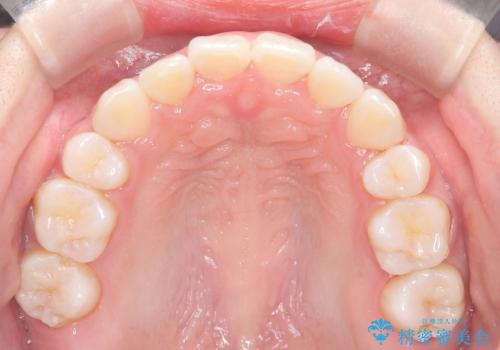

八重歯を改善!美しい口元を実現するハーフリンガル矯正

- 前歯のガタツキと口元のコンプレックスを解消するために来院されました。

ハーフリンガルワイヤー矯正で治療を開始しました。

ハーフリンガル矯正は、見た目を気にせずに矯正治療ができる方法です。この治療法は、八重歯や前歯のガタツキを効果的に改善します。特徴として、ワイヤーが上の歯の裏側に装着されるため、装置が外から見えません。これにより、治療中も自然な笑顔を保ちながら安心して治療を続けることができます。歯並びの悩みを持つ方にとって、非常に魅力的な選択肢です。